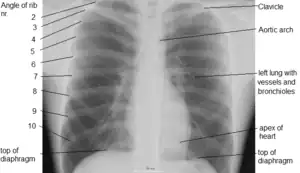

A chest radiograph with the angle parts of the ribs and some other landmarks labeled.

In the average person, the diaphragm should be intersected by the 5th to 7th anterior ribs at the mid-clavicular line, and 9 to 10 posterior ribs should be viewable on a normal PA inspiratory film. An increase in the number of viewable ribs implies hyperinflation, as can occur, for example, with obstructive lung disease or foreign body aspiration. A decrease implies hypoventilation, as can occur with restrictive lung disease, pleural effusions or atelectasis. Underexpansion can also cause interstitial markings due to parenchymal crowding, which can mimic the appearance of interstitial lung disease. Enlargement of the right descending pulmonary artery can indirectly reflect changes of pulmonary hypertension, with a size greater than 16 mm abnormal in men and 15 mm in women.[6]

Appropriate penetration of the film can be assessed by faint visualization of the thoracic spines and lung markings behind the heart. The right diaphragm is usually higher than the left, with the liver being situated beneath it in the abdomen. The minor fissure can sometimes be seen on the right as a thin horizontal line at the level of the fifth or sixth rib. Splaying of the carina can also suggest a tumor or process in the middle mediastinum or enlargement of the left atrium, with a normal angle of approximately 60 degrees. The right paratracheal stripe is also important to assess, as it can reflect a process in the posterior mediastinum, in particular the spine or paraspinal soft tissues; normally it should measure 3 mm or less. The left paratracheal stripe is more variable and only seen in 25% of normal patients on posteroanterior views.[7]